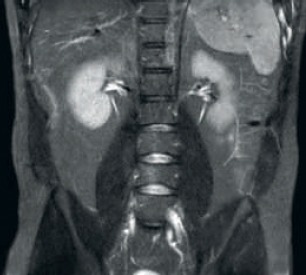

Результат: улучшенное соотношение сигнал/шум и разрешение изображения

Улучшенная согласованность и качество изображений Технология приема РЧ-сигнала dStream выполняет оцифровку МР-сигнала прямо в РЧ-катушке, что позволяет увеличить соотношение сигнал/шум на 40% (макс.)* для всех изображений. Оптимизация рабочего процесса и повышение пропускной способности Задняя катушка, встроенная в деку стола, позволяет избежать дополнительных действий с ней в 60% исследований. Легкие передние катушки, соответствующие анатомическим областям, можно перемещать самостоятельно, а однокабельное соединение делает рабочий процесс проще и быстрее.